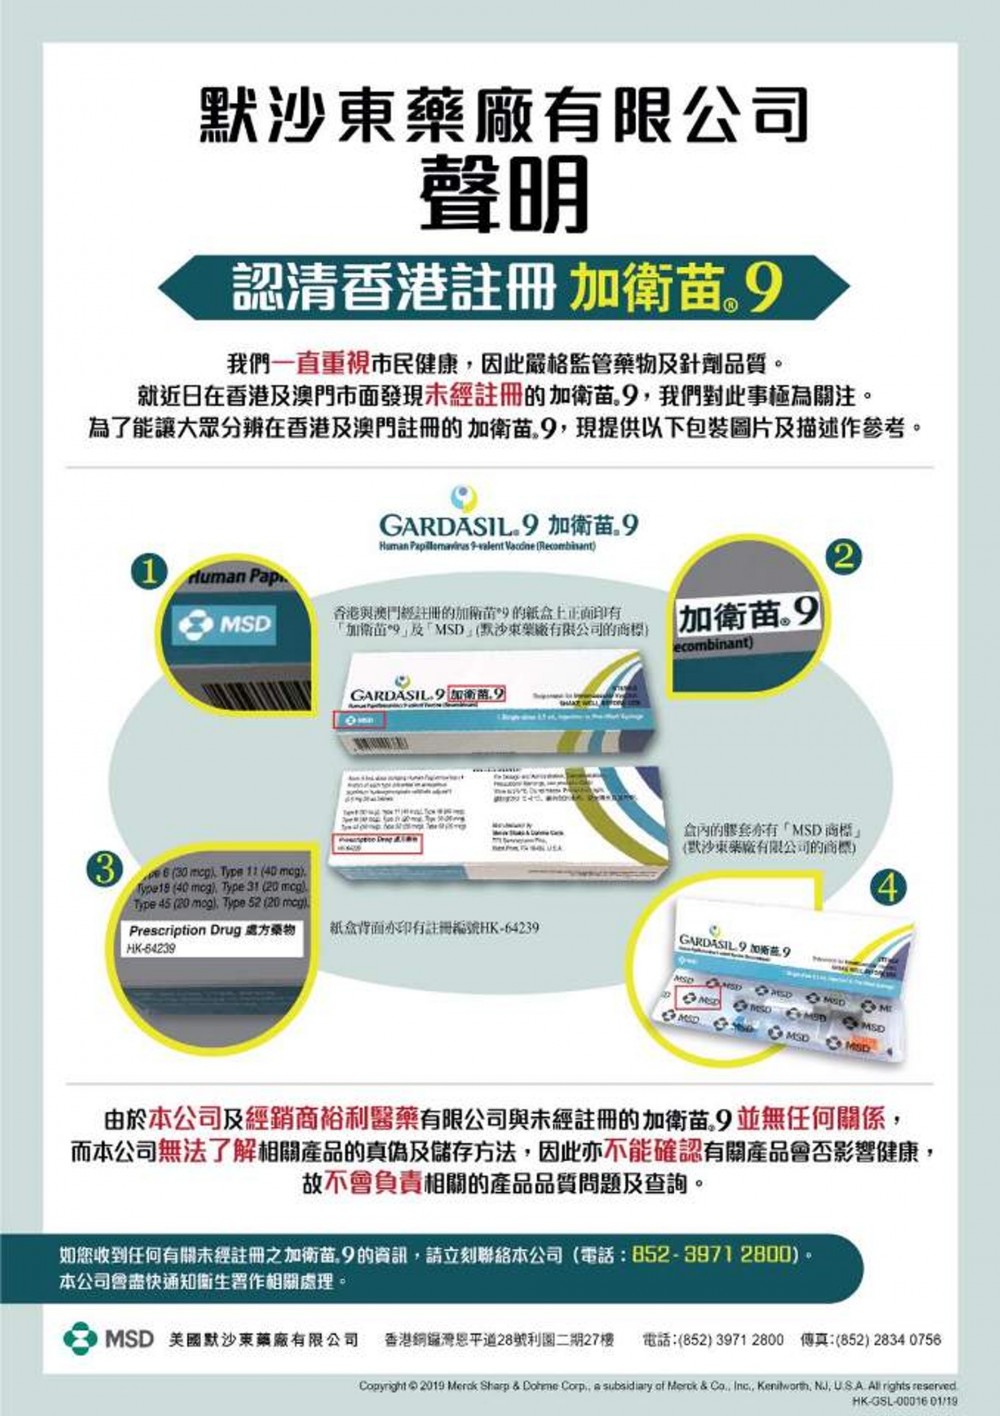

5/ 如何分辨真偽?

作為九價HPV疫苗供應商的默沙東藥廠,就發通告提醒市民,疫苗包裝盒共有四項防偽特徵,包括香港和澳門經註冊的九價HPV疫苗的紙盒正面印有「加衛苗®9」及「MSD」,即默沙東藥廠有限公司的商標、紙盒背面印有註冊編號HK-64239、盒內膠套的錫紙亦有「MSD」商標。